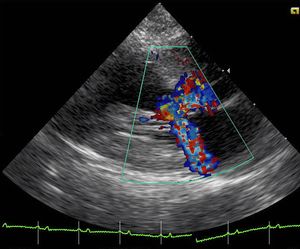

비후성 심근병증(HCM)의 폐쇄성 변이형은 비대성 폐쇄성 심근병증(HOCM)이며, 과거에는 특발성 비대성 상심실하 협착증(IHSS) 또는 비대칭적 중격 비대(ASH)로 불렸다.[34] 좌심실 유출로 폐쇄는 일반적으로 심초음파 평가를 통해 진단되며, 최고 좌심실 유출로 기울기가 30 mmHg 이상인 경우로 정의된다.[33]

심실 비대는 좌심실 유출로(LVOT)를 가로지르는 역동적인 압력 기울기를 유발하며, 이는 수축기 동안 유출로의 추가적인 협착과 관련이 있다. 승모판 엽이 중격 쪽으로 당겨지면서 유출 폐쇄에 기여한다. 이러한 당김은 여러 제안된 메커니즘에 의해 발생한다고 생각되는데, 좁아진 유출로를 통과하는 혈류가 더 높은 속도를 갖게 되고, 벤투리 효과를 통해 압력이 낮아지기 때문이다.[16] 이 낮은 압력은 승모판의 전방 엽을 유출로로 당기게 하여 추가적인 폐쇄를 유발한다.[31]